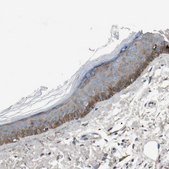

Macrophage-stimulating protein receptor (MST1R) belongs to the MET receptor tyrosine kinase family. It is expressed in keratinocytes and macrophages.

The Human Protein Atlas project can be subdivided into three efforts: Human Tissue Atlas, Cancer Atlas, and Human Cell Atlas. The antibodies that have been generated in support of the Tissue and Cancer Atlas projects have been tested by immunohistochemistry against hundreds of normal and disease tissues and through the recent efforts of the Human Cell Atlas project, many have been characterized by immunofluorescence to map the human proteome not only at the tissue level but now at the subcellular level. These images and the collection of this vast data set can be viewed on the Human Protein Atlas (HPA) site by clicking on the Image Gallery link. We also provide Prestige Antibodies® protocols and other useful information.

• IHC tissue array of 44 normal human tissues and 20 of the most common cancer type tissues.